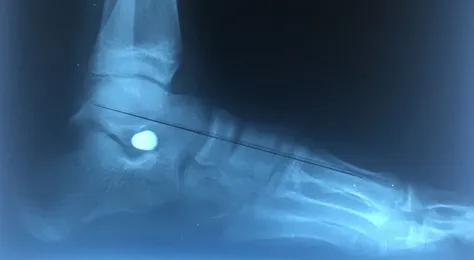

Pre and Postop X-rays Subtalar Joint Implant (Below)

Pre and Postop Subtalar Implant and Percutaneous Achilles Lengthening Below. The first pics show wedging of the distal tibia physis causing ankle valgus due to constant pressure caused by the severity of the flatfoot (JT)